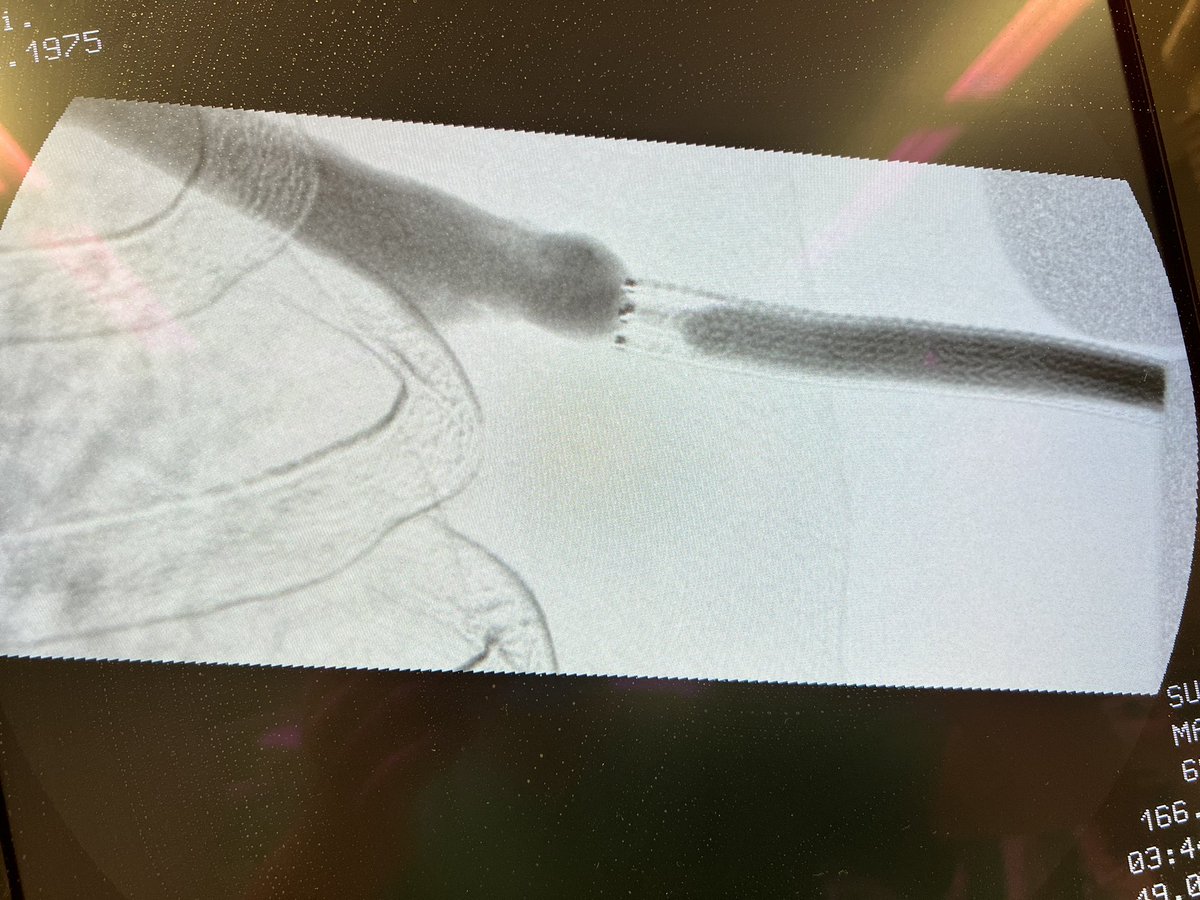

9 months old upper arm axillo-axillary loop AVG created using

#VORTECtechnique. Now high venous pressures and this

angiogram. What you gonna do? #VascularAccessCenter#Hamburg#Barmbek@wasse_m@jimbog_76@CHICKVIR 1/2 pic.twitter.com/kKsO0dGapw